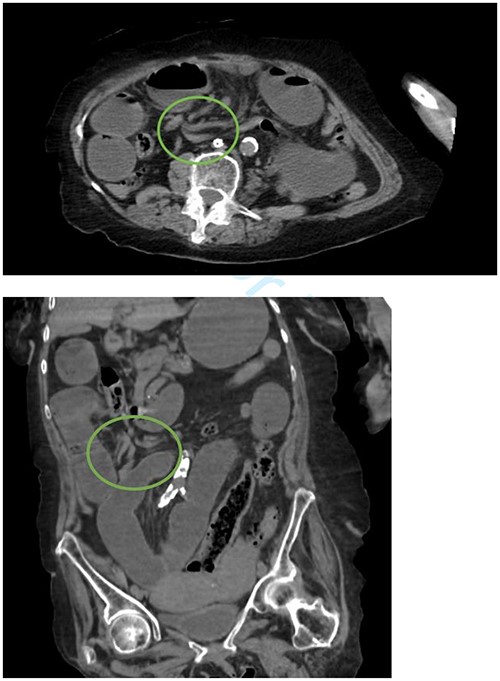

Initial vital signs included temperature of 98.3°F, respiratory rate of 15 breaths per minute, blood pressure of 140/75 mm of mercury, and pulse of 80 beats per minute. Upon evaluation, the patient was noted to be disoriented. Abdominal exam revealed a benign abdomen without distention, a right paramedian surgical scar, and vertical lower abdominal scar, both well healed. Labs revealed white blood cells of 14.22 white blood cells per microliter and lactate of 2.80 mmol per liter. Computed tomography (CT) showed dilated loops of proximal small bowel with twisting of the superior mesenteric vessels consistent with midgut volvulus (Fig. 1).

Whirlpool sign indicated by a circle representing a twisting of the mesentery around the superior mesenteric artery.